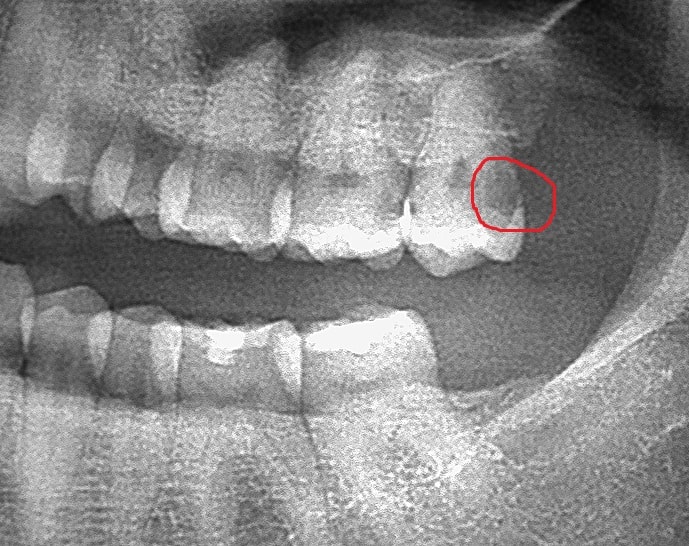

Wisdom teeth can be very hard to clean with a tooth brush. For that reason they can develop cavities. If the cavity grows to reach the nerve of the tooth, the patient will experience pain. It’s usually best to extract wisdom teeth with large cavities.